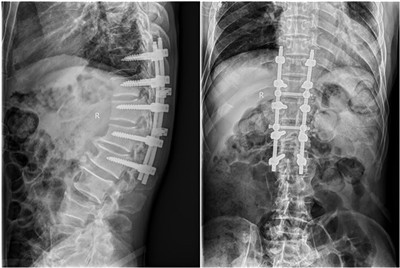

入院后经科室集体讨论,反复研究,压迫如此广泛严重,术中稍有不慎,即有可能致患者瘫痪,手术风险极大。与患者家属充分沟通后,高宗强副主任医师最终决定为患者施行后路长节段胸椎椎板减压并钉棒内固定术。先给医院上报重大手术,在11月20日晨9时许,兰宾尚主任、张纯主任现场把关,王芳术中电生理监测,李有才教授、何家璇进行全麻,由高宗强副主任医师主刀,刘若西博士、刘鹏飞规培医师协助下于在全麻下行后路减压钉棒内固定术(从胸10/11-腰1/2节段),术中发现脊髓压迫极其严重,且骨化块异常坚硬,钙化的黄韧带将硬膜囊紧紧卡死并紧密粘连,术中邀请神外王睿智副主任医师修补硬膜囊,手术持续约8小时,于下午5时许顺利结束。现患者神经功能恢复良好,术前明显增高的肌张力恢复正常,踝阵挛消失(图4),难以自控的抽动消失。

图4